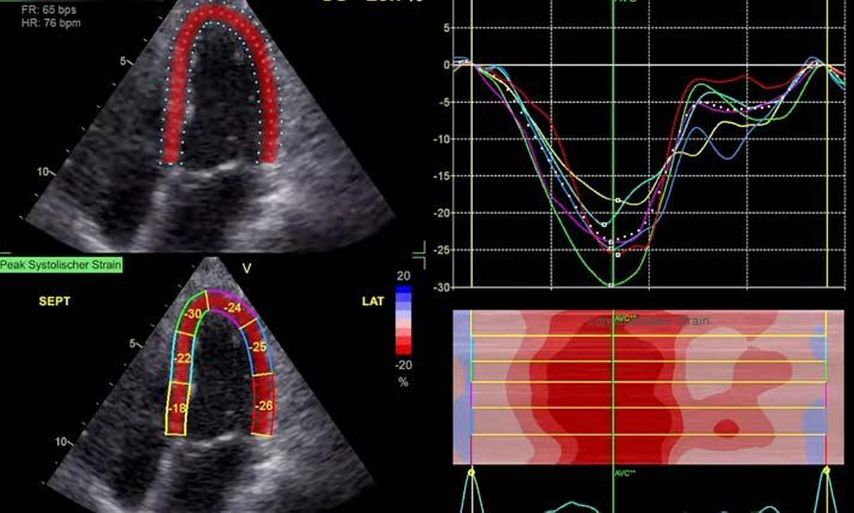

Im Echolabor des Pyhrn-Eisenwurzen Klinikums Steyr wird jede Form der Myokardwandverdickung mittels einer vollständigen Standardechokardiografie untersucht.2 Dabei wird auch ein Fokus auf die kontrastmittelunterstützte Sonografie gelegt, um die tatsächliche Dicke des Myokards zu vermessen.3 Die Verdickung sollte optimalerweise mittels 3D-LV-Massenmessung erfolgen. Die Messung im 2D-Bild ist dahingehend unterlegen. Ebenso wird jede Myokardwandverdickung mittels 2D-„strain imaging“ in der transthorakalen Echokardiografie (TTE) untersucht.4–6 Der „strain“ ist eine Messung der longitudinalen Funktion des Herzens (Video 1).

Der erste Fall beschäftigt sich mit einem Patienten mit einer hypertrophen Kardiomyopathie (HCMP). Er gibt eine deutliche Belastungsdyspnoe sowie einen ausgeprägten Leistungsknick an. Es wurde infolgedessen eine Untersuchung mittels standardisierter Echokardiografie inklusive „strain imaging“ durchgeführt. Der globale longitudinale „strain“ (GLS) mit –16% in Ruhe war gering reduziert. Es konnte kein relevanter LVOT-Gradient in Ruhe nachgewiesen werden. In der Belastungssituation (Handgrip, Valsalva, Kniebeugen und als Vorbereitung zur Untersuchung ein ausgiebiges Frühstück und Kaffee sowie ein am Vorabend konsumiertes Bier) konnte bei Kniebeugen mit einer Herzfrequenz von 126/min ein Spitzengradient bis 52mmHg dargestellt werden. Somit ergibt sich die Diagnose einer HOCMP mit einem belastungsinduzierten Gradienten. Bei bereits bestehender und ausgereizter Therapie unter Betablocker besteht die Indikation zur Therapie mittels des kardialen Myosininhibitors Mavacamten (Klasse-IIa-Empfehlung laut ESC).1 Darunter verbesserte sich die klinische Situation des Patienten deutlich, der Patient konnte uneingeschränkt Sport ausüben. Über die Zeit kam es zu einer geringen Reduktion der LV-Masse und einer geringen Zunahme des LV-„strain“. Die Belastungssituation zeigte durchwegs normale „strain“-Werte mit –20% (mit regionaler Reduktion bei Myokardwandverdickung im Sinne einer Hypertrophie). Die myokardiale Arbeit beim konkreten Patientenfall ist ebenso in Ruhe im grenzwertigen und unter Belastung im guten Normalbereich.6,8,9 Der Patient ist derzeit unter 5mg Mavacamten einmal täglich optimal eingestellt. Die EF in Ruhe ist konstant bei 50–55%. In Video 2 werden unterschiedliche Gradienten dargestellt, um eine HOCMP mit LVOTO von z.B. einer Mitralklappeninsuffizienz zu unterscheiden.Die Verdachtsdiagnose wurde mithilfe der Echokardiografie gestellt und durch das septal betonte „patchy“ LGE im MRT bestätigt.1,5

Andere Formen der Myokardwandverdickung, die mit „strain“ und MRT gut dargestellt werden können, sind einerseits die Differenzierung der Auswirkung der arteriellen Hypertonie (weiblich, 72a) bei Vorliegen einer Herzinsuffizienz mit normaler EF, einem GLS von –15,4%, einem LA-„strain“, in Reservoirphase 25% bei gering verlängerten T1-Zeiten im MRT. Andererseits kann Steroidabusus (männlich, 44a) zu einem reduzierten „strain“ mit gering verlängerten T1-Zeiten und einer Normalisierung der bildgebenden Befunde nach 2 Jahren nach Absetzen führen bzw. eine Mitochondriopathie (männlich, 32a) zu einer unklaren Myokardverdickung mit diffus reduziertem „strain“ und reduzierter LV-Funktion.4,11,12